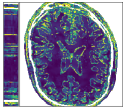

Figure 3 shows an example of a single frame of the reconstructed MR image sequences for an acceleration factor of using several approaches. We show the reconstructions that correspond to the single scalar parameter as well as to the scalar parameter pair (one spatial and one temporal) which are the parameters that maximize the PSNR of entire cine MR image and are obtained via a grid search by making use of the corresponding ground truth image. We also show the results that correspond to the parameters and which are respectively the single and the pair of scalar parameters that on average maximize the PSNR over the training set. These were obtained by treating the scalar regularization parameters as trainable parameters and training them by minimizing (33). We finally show the results for our estimated parameter-map with the proposed method. As observed, for all choices of the regularization parameters, the error with respect to the target image was significantly reduced compared to the initial zero-filled reconstruction. Further, we can see how the use of the estimated parameter-map yields the most accurate reconstruction and the best preservation of image details.

Figure 4 summarizes the results obtained over the test set with the help of box-plots. Compared to the initial zero-filled reconstruction, an improvement is clearly visible for all choices of the regularization parameter with respect to all reported measures and for all acceleration factors. In addition we see how allowing the temporal direction to be differently regularized than the two spatial dimensions positively influences the results compared to having one global parameter (orange vs blue). Last, we see how using the proposed method to estimate an entire spatio-temporal parameter-map further surpasses the scalar regularization parameter-maps (green vs orange and blue), especially in terms of SSIM. Table 1 lists the mean and the standard deviation of all TV-reconstructions. The results are consistent with the ones from the box-plots.

Figure 5 shows an example of a spatio-temporal regularization parameter-map which was estimated using the proposed approach for an acceleration factor of . The network estimates the regularization parameter-map to be pointwise relatively consistenly higher than the spatially required regularization. This result is in fact expected as the temporal dimension is the one for which the gradients of the images are the sparsest because of the high temporal correlation. Further, we see how the network consistently predicts both the spatial regularization as well as the temporal regularization to be less strong in the area where most of the movement is expected, i.e. in the cardiac region.